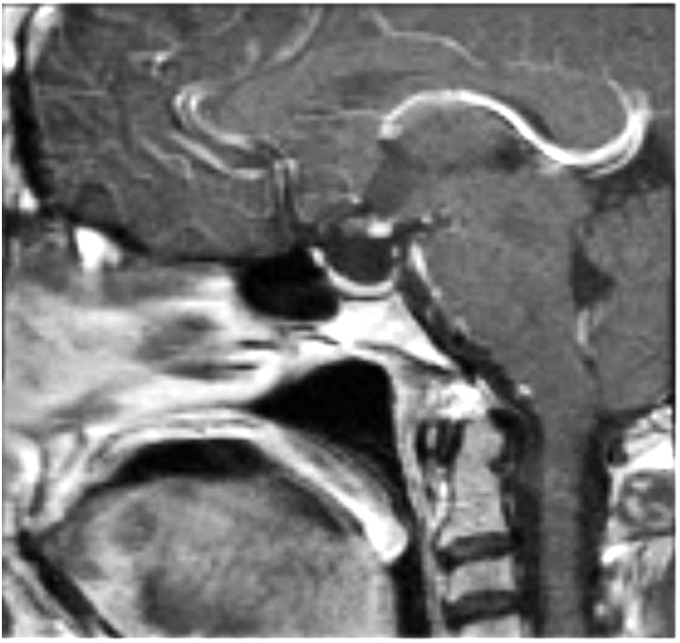

A 42-year-old-female presented for evaluation of premature menopause, weight loss, and occasional dizziness. On examination she had short stature and absent secondary sexual features. Laboratory tests were consistent with hypopituitarism with follicle stimulating hormone 0.5 mIU/mL (16.7-113); luteinizing hormone 1.2 mIU/mL (10.8-58.6); prolactin 10.4 ng/mL (2.7-19.6); estradiol 20 pg/mL; cortisol 2 mcg/dL (6.7-22.6); adrenocorticotropic hormone 18 pg/mL (6-50); thyroid stimulating hormone 10.33 uIU/mL (0.28-3.8); free T4 0.41 ng/dL (0.58-1.64); insulin like growth factor-1 −3.7 SD (17 ng/mL) (52-328); and adrenocorticotropic hormone stimulation confirmed secondary adrenal insufficiency. The magnetic resonance imaging of the brain revealed an ectopic posterior pituitary with a partially empty sella, absence of the pituitary stalk, and a small anterior pituitary. The patient was initiated on replacement hormones with improvement in her symptoms.